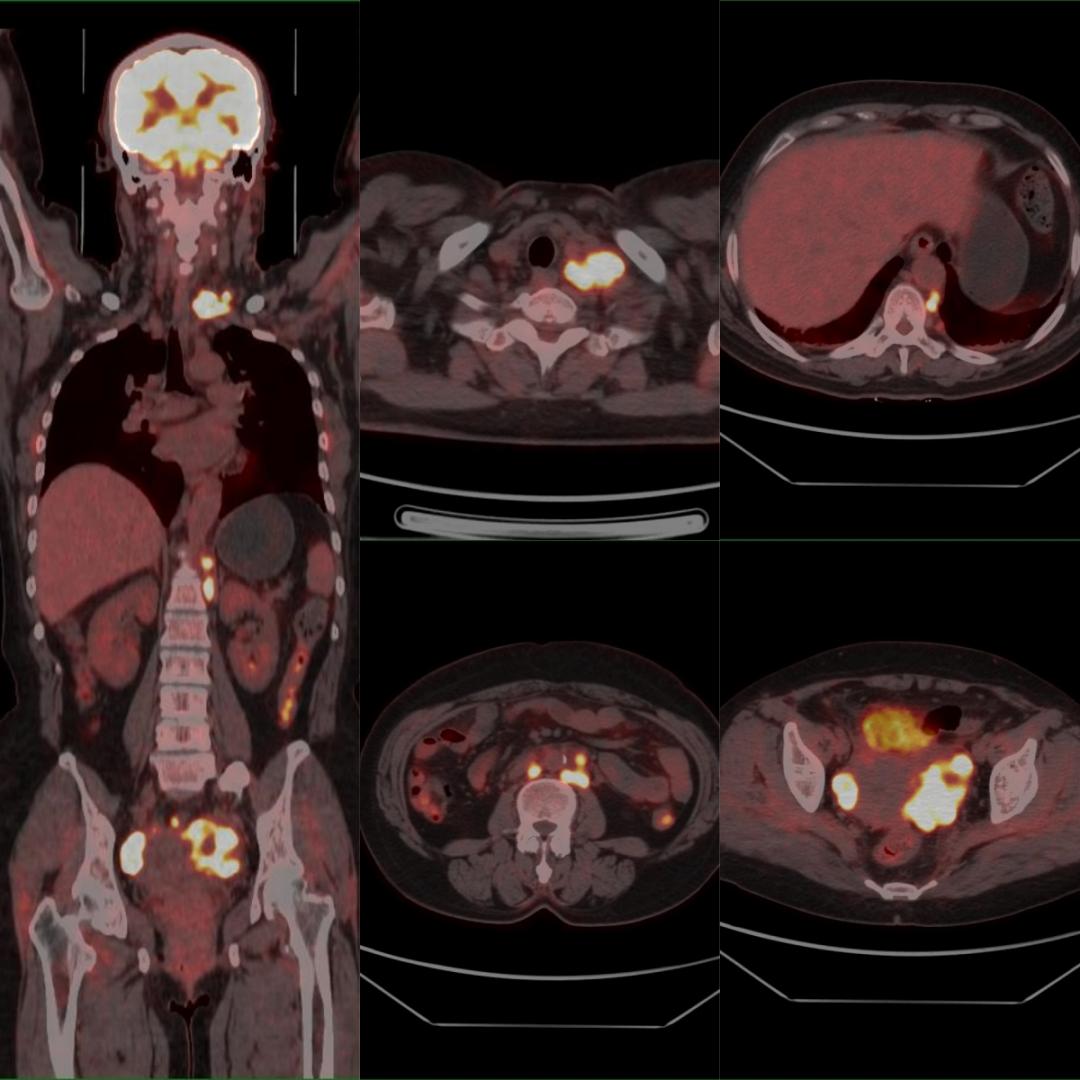

患者以“甲狀腺占位、左鎖骨上占位”入院,行超聲引導下左鎖骨上窩腫物穿刺術(shù),病理:考慮分化差的癌,結(jié)合免疫組化結(jié)果,考慮轉(zhuǎn)移的腺癌,建議檢查乳腺、肺等部位。為明確腫瘤原發(fā)灶,行PET/CT檢查,示:雙側(cè)卵巢、盆腔、腹膜后、后縱隔、左側(cè)鎖骨上多發(fā)高代謝病灶,診斷為雙側(cè)卵巢癌伴多發(fā)淋巴結(jié)轉(zhuǎn)移,后行手術(shù)、化療等治療。

雙側(cè)卵巢Ca伴多發(fā)淋巴結(jié)轉(zhuǎn)移

PET/CT用于卵巢癌淋巴結(jié)轉(zhuǎn)移的術(shù)前評估,其敏感度為83.3%,特異度為98.2%,準確率為95.6%。因此可作為卵巢癌術(shù)前評估淋巴結(jié)轉(zhuǎn)移的重要方法。

本例患者初步診斷左側(cè)鎖骨上淋巴結(jié)不明來源轉(zhuǎn)移癌,臨床選擇PET/CT來尋找原發(fā)灶。PET/CT發(fā)現(xiàn)了非預期的原發(fā)灶(左側(cè)鎖骨上淋巴結(jié)轉(zhuǎn)移癌最常見的原發(fā)腫瘤并非卵巢,且初步病理提示排查乳腺和肺),大幅縮短了篩查原發(fā)灶的時間,減少了非針對性的檢查,節(jié)約了寶貴的資金,患者得到及時、科學的治療,獲益明顯。